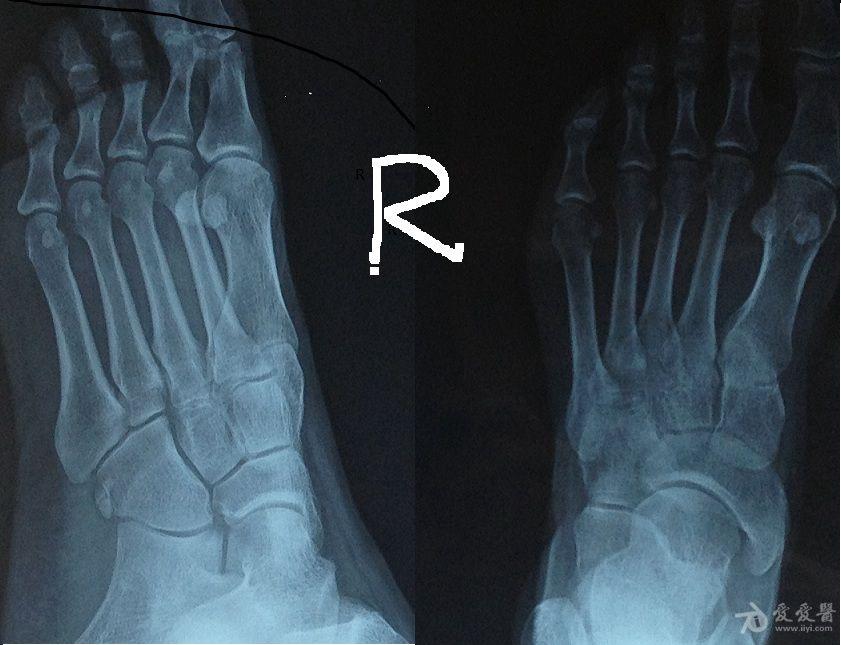

一旦钙严重缺乏,骨头就变得疏松起来,坚硬度下降,就形成了老人中常见的骨质疏松症。对老年女性尤其如此,因为雌激素对于成骨过程至关重要,绝经期女性雌激素分泌大幅度下降,导致骨质变得像蜂窝一样,疏松易断。在全世界范围内,患骨质疏松症的人群中,80%是女性,其中50岁以上的大约占1/10,70岁以上的占1/5,而男性的这个比例大约是7%。